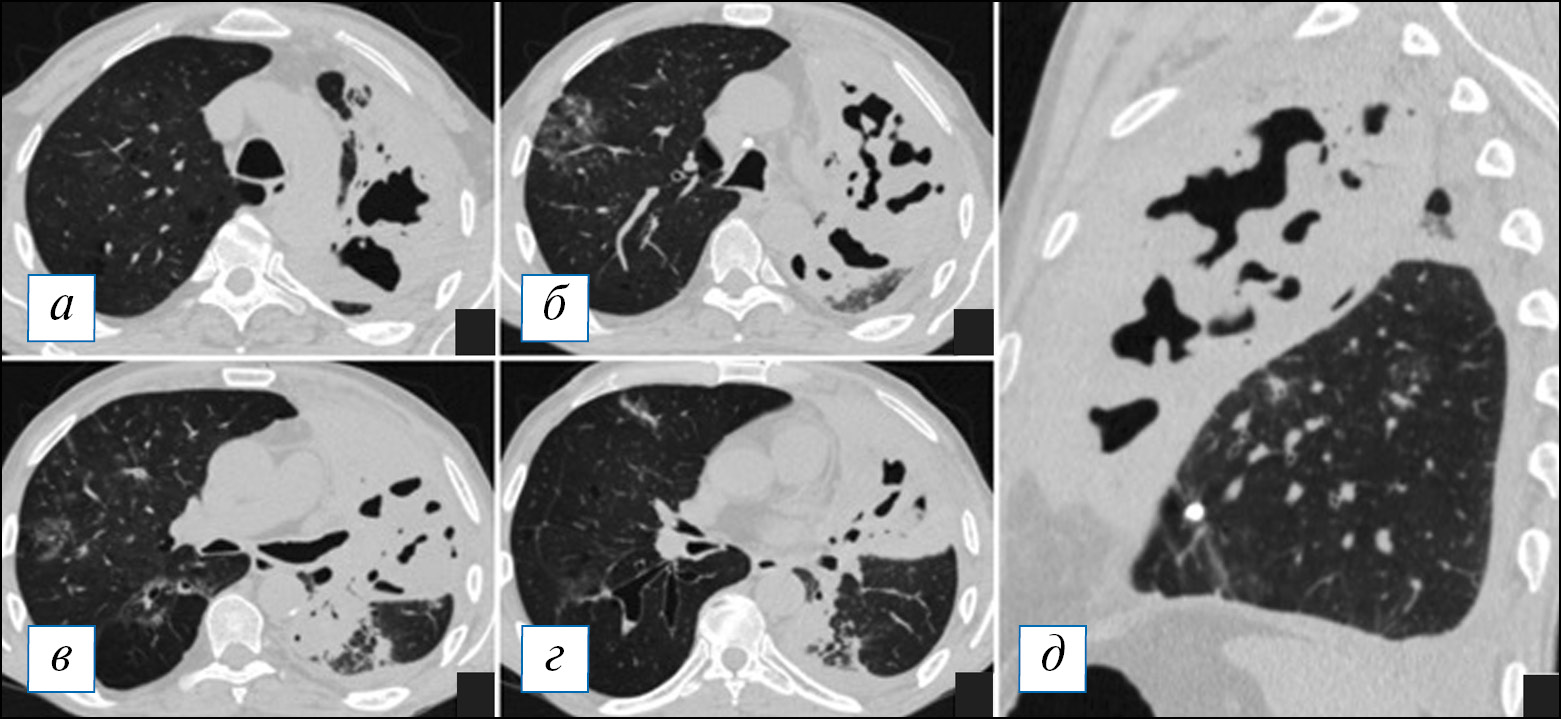

При проведении КТ органов грудной клетки отмечается уплотнение, чаще в виде консолидации или по смешанному типу, в сочетании с «матовым стеклом» пораженной части легкого, которая может быть несколько увеличена в размерах (рис. 2, Б), что объясняется скоплением экссудата и отеком легочной паренхимы по типу «выбухающей борозды». На фоне уплотнения быстро происходит деструкция легочной ткани в виде множественных очагов или более обширных участков; в начале этого процесса в полостях распада можно наблюдать некоторое количество содержимого с горизонтальным уровнем; секвестры нехарактерны (рис. 2). Внутренняя стенка полостей имеет четкий контур, что объясняется дренированием содержимого через бронхи, которые в ряде случаев прослеживаются (рис. 3). Может отмечаться выраженная реакция плевры, с развитием выпота или даже эмпиемы и пиопневмоторакса, особенно при формировании свища [8, 9, 40]. Негативными последствиями некротизирующей пневмонии может являться формирование фиброза с бронхоэктазами, персистирование полостей распада при отсутствии их спадения, а также облитерация плевральной полости на уровне воспалительного процесса [39].

Рис. 2. Компьютерная томография органов грудной клетки в аксиальной проекции (а–г). Двусторонняя полисегментарная пневмония. С обеих сторон в легких, больше справа, имеются инфильтраты, на фоне которых просматриваются полости различного размера без жидкостного содержимого. Незначительный пневмомедиастинум. [Изображения из архива авторов]. / Fig. 2. Chest CT, axial projection (а–г). Bilateral polysegmental pneumonia. On both sides in the lungs, more to the right, there are infiltrates and cavities of various sizes without liquid content. Minor pneumomediastinum. [Images from the authors’ archive].

Рис. 3. Компьютерная томография органов грудной клетки в аксиальной проекции (а, б). Пневмоническая инфильтрация в верхней доле слева с деструкциями. Имеются участки по типу «шальной исчерченности» в сочетании с консолидацией, на фоне которой обнаруживаются разнокалиберные полости распада без содержимого, наружный их контур не прослеживается. [Изображения из архива авторов]. / Fig. 3. Chest CT, axial projection (а, б). Pneumonic infiltration in the upper lobe on the left with destructions. There are areas of a «crazy paving» sign in combination with consolidation, against the background of which one can see destructive cavities of various sizes without content, their outer contour is not traced. [Images from the authors’ archive].